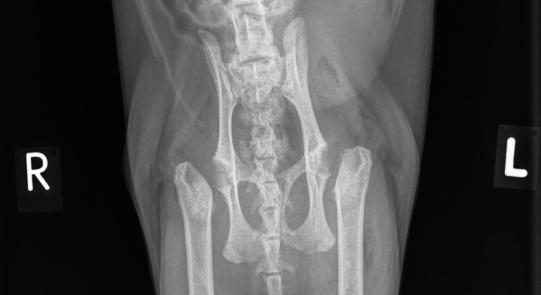

Charly wird orthopädisch untersucht. Er zeigt ein stark verändertes Gangbild in der Hinterhand: Die Katze läuft mit gekrümmtem Rücken, untergeschobenen Hinterbeinen und wie auf Eiern. Die Oberschenkelmuskulatur ist beidseits schlecht ausgebildet, und das Strecken der Hüftgelenke ist ganz offensichtlich schmerzhaft. In einer kurzen Sedation werden deshalb Röntgenaufnahmen des Beckens und der Hüftgelenke angefertigt. Hier ist die Ursache des Problems ersichtlich: An beiden Oberschenkelhälsen ist eine Bruchlinie zu sehen; die Oberschenkelköpfe sind beidseits vom Oberschenkelhals-Knochen abgebrochen!

Die Röntgenveränderungen erklären die Gangprobleme von Charly vollständig - er leidet unter einer beidseitigen sogenannten metaphysealen Osteopathie der Oberschenkelhälse.

Die Therapie des Problems besteht wie bei einem "normalen" Oberschenkelhalsbruch bei der Katze in der chirurgischen Entfernung der abgebrochenen Oberschenkel-Gelenksköpfe. Dieses Verfahren ist deutlich einfacher und erfolgsversprechender als der Versuch, die Gelenksköpfe wieder am Oberschenkel zu befestigen. Da aufgrund der langen Krankheitsdauer mit viel Narbengewebe und einem schwierigen Zugang zum Operationsgebiet gerechnet werden muss, überweisen wir Charly für die Operation an eine chirurgische Spezialklinik. Zehn Tage nach der Operation ziehen wir die Fäden - Charly benutzt die Hinterbeine schon wieder recht gut; es ist zu erwarten, dass nach der Rekonvaleszenz sein Gang viel besser sein wird als vor der OP und die Katze vor allem schmerzfrei sein wird.